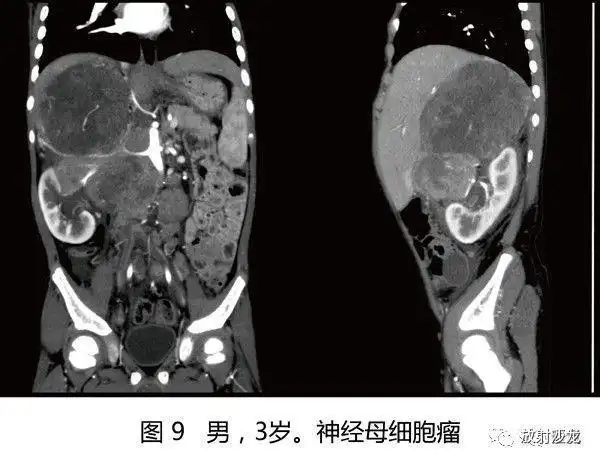

4岁女童腹膜后神经母细胞瘤

成人腹膜后神经母细胞瘤小圆细胞瘤一例